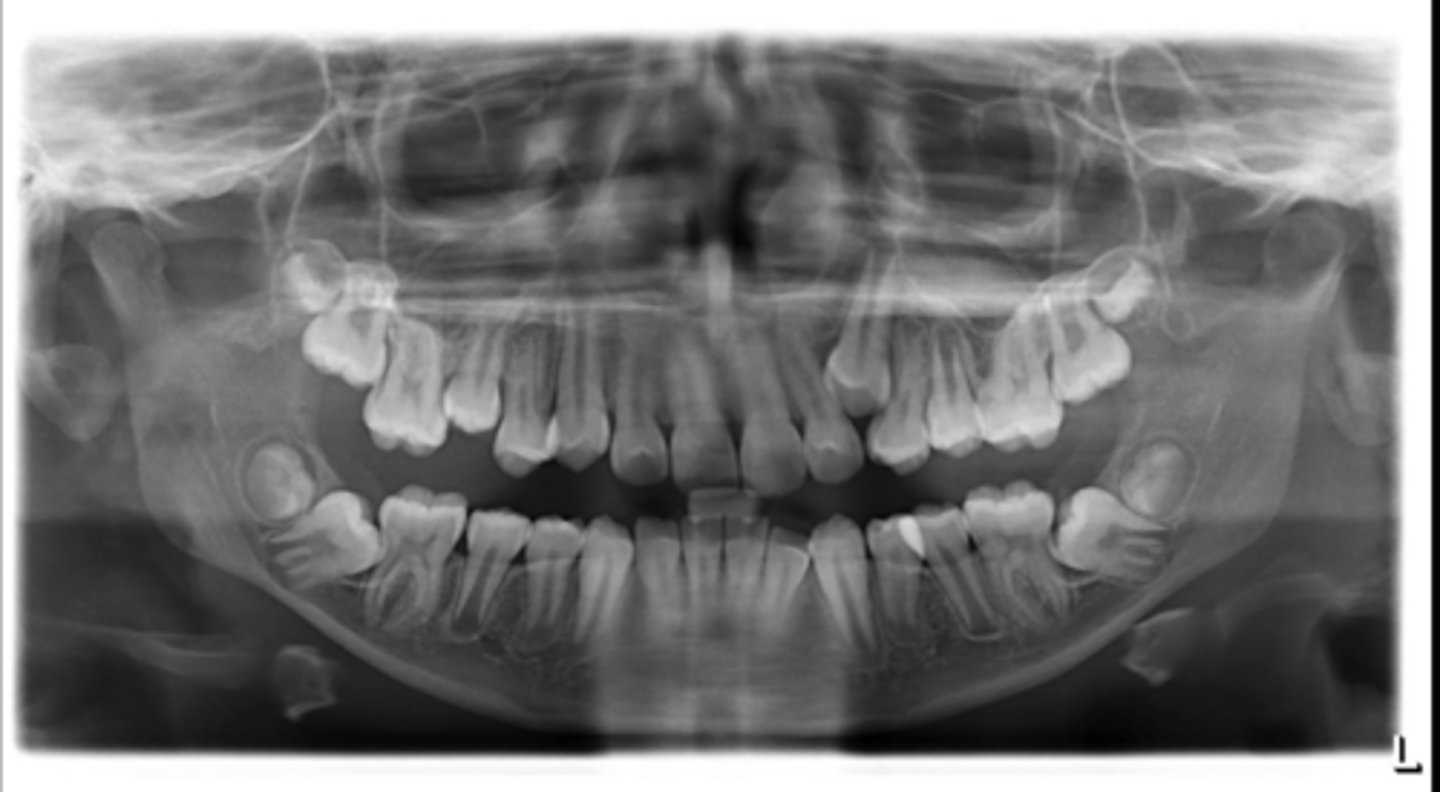

Premolar #13 (unerupted in pano) is more tilted than the opposing side (#4), which indicates an ectopic eruption pattern.

(Primary teeth w/o resorbing roots is also present)

What abnormalities/concerns do you see in this pano?

Third molars and mandibular right second premolar

Are there any congenitally missing teeth in the maxillary arch?

#29 (mandibular right second premolar)

Are there any congenitally missing teeth in the mandibular arch?

mandibular right second molar

Are there any retained primary teeth?

maxillary canines

Are there any impacted teeth?

Yes

Is there crowding?

More or less

Are the condyles symmetrical?

Maybe?

Is there any pathology?

Are there any ankylosed primary teeth?

No, just one in an odd position

Is there any ectopic eruption?

No

Are there supernumerary teeth?